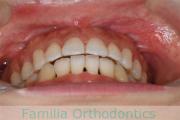

下の前歯が後ろにあるのが気になるとのことで来院されました。非抜歯で行うことも可能でしたが、上下左右から小臼歯抜歯をして治療を行うことをご希望になりました。

マルチブラケット法にて治療を行い、約3年、40回の通院が要でした。

かみ合わせが深い(上の前歯で下の前歯が覆われてしまう)ので、保定をしっかりしないと、また深くなってきてしまいやすいです。

- ≫治療後

-

上顎

下顎

前歯の関係など

右側

正面

左側